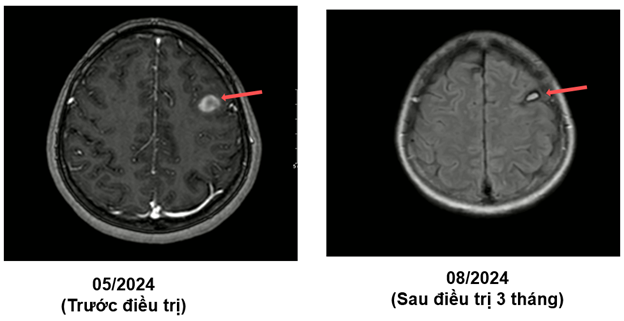

MRI sọ não sau điều trị:

Ct ngực sau điều trị:

Theo dõi định kỳ bằng lâm sàng, chụp CT ngực và MRI sọ não sau 3 tháng, 6 tháng và 15 tháng cho thấy:

- Tổn thương phổi và não giảm kích thước rõ rệt.

- Không xuất hiện tổn thương di căn mới.

- Tình trạng toàn thân ổn định, chất lượng sống được cải thiện.